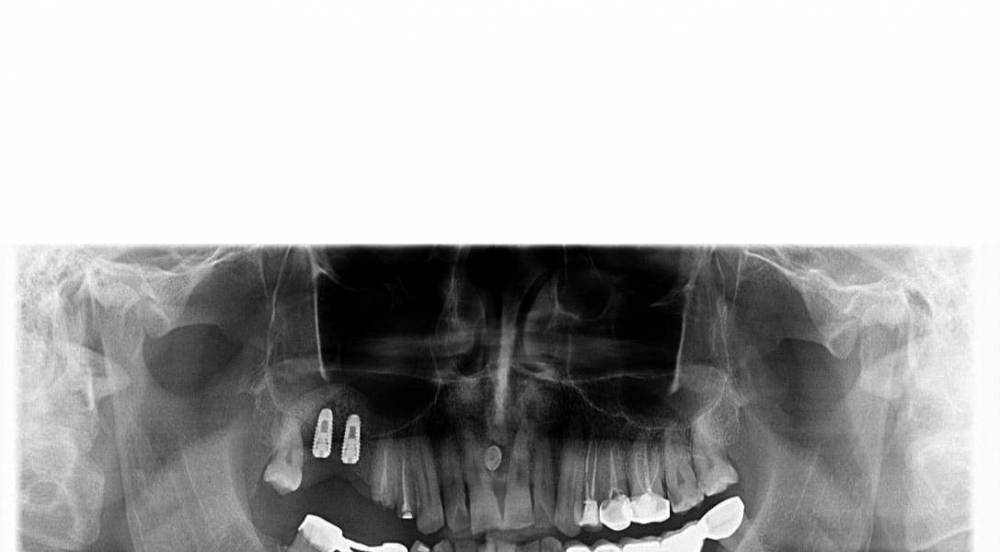

Фаик Исламбеков Опубликовано 1 декабря, 2021 Поделиться Опубликовано 1 декабря, 2021 Здравствуйте.2 недели назад сделал первый открытый синус. Перед началом работы ещё раз перечитал форум повторил для себя все советы и рекомендации. Получился неплохо.Открыл поднял и закрыл Пока тфу тфу вроде нормально. Но потом через несколько дней вспомнил что мембрана одной стороной гладкая а другая сторона шероховатая и не могу вспомнить какая сторона к окну надо было приложить. Поискал ещё раз но ответа не нашел. Если я сделал наоборот плохо? Ссылка на комментарий

Фаик Исламбеков Опубликовано 1 декабря, 2021 Автор Поделиться Опубликовано 1 декабря, 2021 Понедельник второй открытый синус и хочется чтобы все было хорошо. Ссылка на комментарий